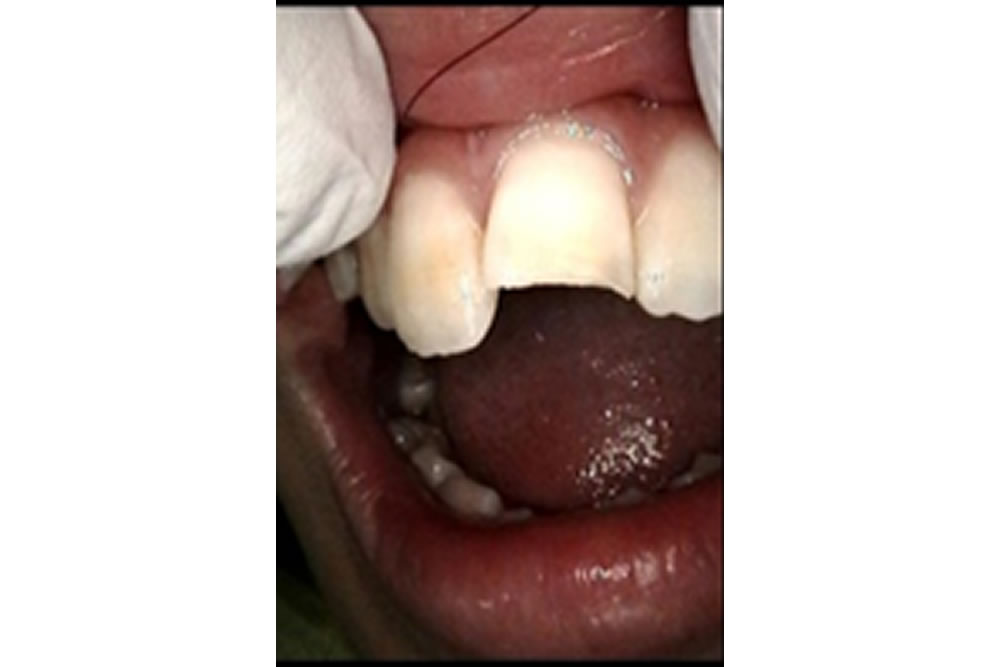

破折した歯をCRにて修復した症例

破折した歯をCRにて修復した症例 こちらの患者さまは、跳び箱で顔面から落ちてぶつけて歯が折れたという外傷により来院されました。 レントゲン撮影を行い、歯根や歯槽骨が折れていないか歯髄(神経)等の確認をとりました。口腔内診 […]